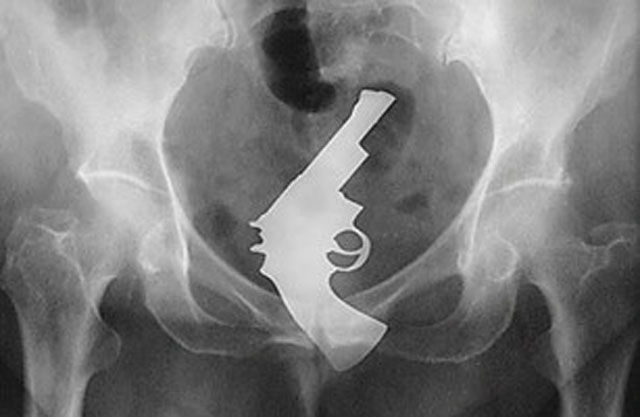

Gun